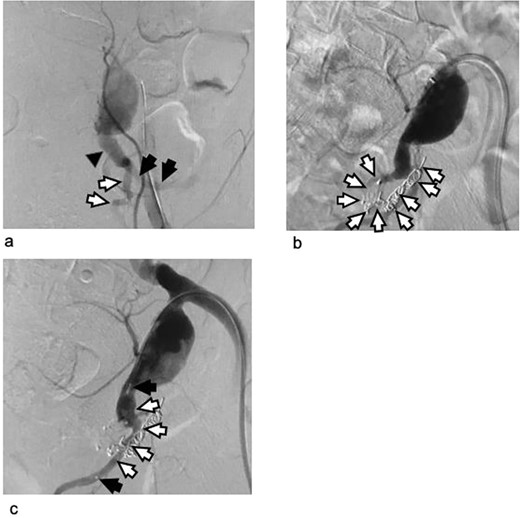

Arteriogram of the left internal iliac artery during the embolization procedure as the first stage of hybrid intervention. (a) Arteriogram before embolization: The left internal iliac artery stem distal to the aneurysm (black triangle) and the anterior (white arrows) and posterior division of the internal iliac artery (black arrows) are shown. (b) Arteriogram after coiling of the posterior division of the left internal iliac artery: Metal coils are visible from the posterior division of the left internal iliac artery to the superior gluteal artery. The microcoil was used because it provides good control in these narrow and tortuous arteries. (c) Arteriogram after vascular plug deployment: The left internal iliac artery stem and its anterior division were embolized using an Amplatzer vascular plug because they were wide and straight enough to insert the 5 Fr guiding catheter. Triangles: the vascular plug. The black arrows indicate the tip of the plug. The blood flow in the artery persisted after the plug had been deployed. The completion of embolization with metal devices needs time.